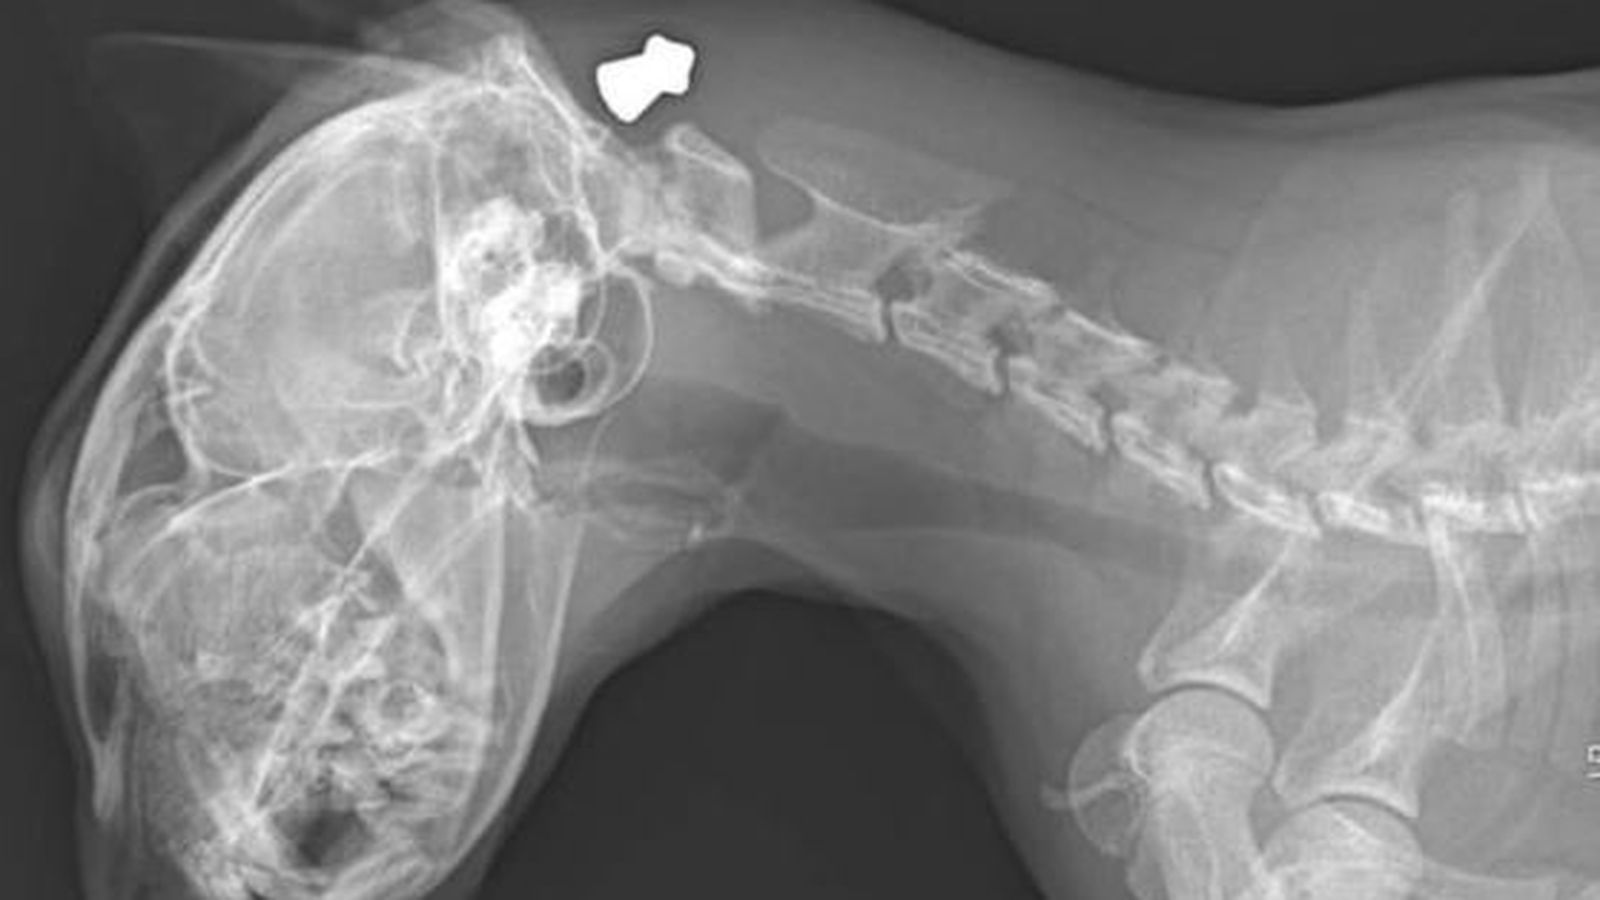

Una família de Crevillent ha denunciat l’intent d’assassinat del seu gat amb una arma de foc, concretament una carabina d’aire comprimit, segons han denunciat a les xarxes socials. L’animal ha sigut intervingut d’urgència i el seu cuidador han interposat una denúncia a la Guàrdia Civil per a tractar de trobar la persona responsable.